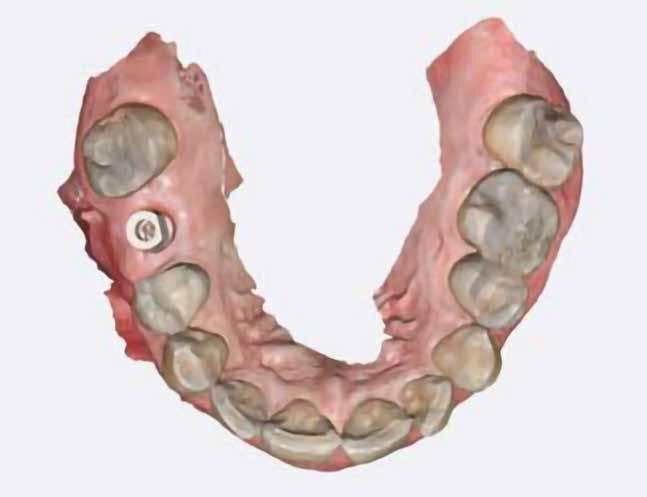

Digitális intraorális scan

Egy héttel a második műtét után intraorális szkennelést végeztünk Medit i500 scannerrel (Medit), a gyártó szkennelési protokollját követve (7. ábra). A gyógyulási csavarok eltávolítása után CERALOG scanbodykat (PEEK-titánötvözet csavar) helyeztünk el az implantátumokba. A fogszín meghatározását digitálisan, a Rayplicker (Borea) segítségével végeztük. A protetikai pótlás tervezéséhez poliphenilszulfon felépítményeket alkalmaztunk. Minden koronát digitálisan rendeltünk ugyanabból a fogászati laboratóriumból, és kerámiakoronákat választottunk minden esetben.

7. a–d ábra: Digitális intraorális szkennelések az implantátum felszabadítása után. 1. eset (a). 2. eset (b). 3. eset (c), 4. eset (d).

tottuk (az okklúziós koncepciók alapján az implantációs pótlások nem voltak vezető fogak, és csak könnyű érintkezéseket alakítottunk ki, amelyeket artikulációs papírral ellenőriztünk). A páciensek instrukciókat kaptak a megfelelő szájhigiénére vonatkozóan, összpontosítva a fogköz kefékkel történő tisztítására. Végső kontroll röntgenfelvétel készült. A PEEK felépítmény nem radioopák, így az implantátum és a korona közötti távolság könnyen meghatározható a röntgenfelvételen: a felépítmény megfelelően illeszkedik az implantátumban, ha az implantátum válla és a korona alsó széle közötti rés 0,55 mm a röntgenfelvételen (8–11. ábra)